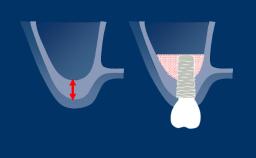

Obtaining detailed information about a patient's medical history is mandatory before any surgical procedure such as implant therapy can be considered in a treatment plan.

Special attention should be paid to patient-related factors that may affect bone healing. These factors can determine whether the patient is a suitable candidate for the planned procedure or if other treatment alternatives should be preferred.